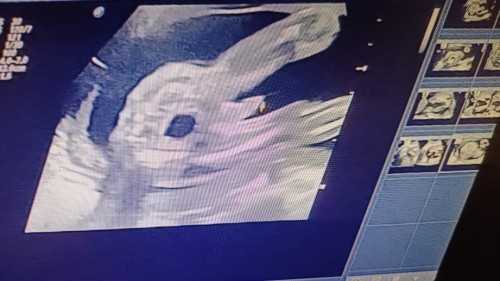

scan berapa week sis. sy pon tgh preggy yg ke 3. mgharap sgt yg nie boboy..

Mcm Boy sbb ada pistol lonjong dekat tgh, tahniah puan🥰🎉

Tahniah.. Boy ni👶🏻 nampak jelas tengah2 tu🥰

boy,terang lg bersuluh tu.